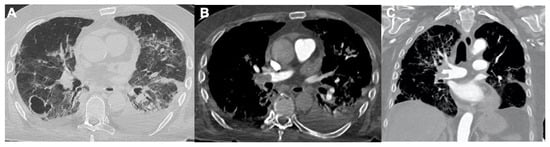

2.1. Pneumonia

2.2. Acute Respiratory Disease Syndrome